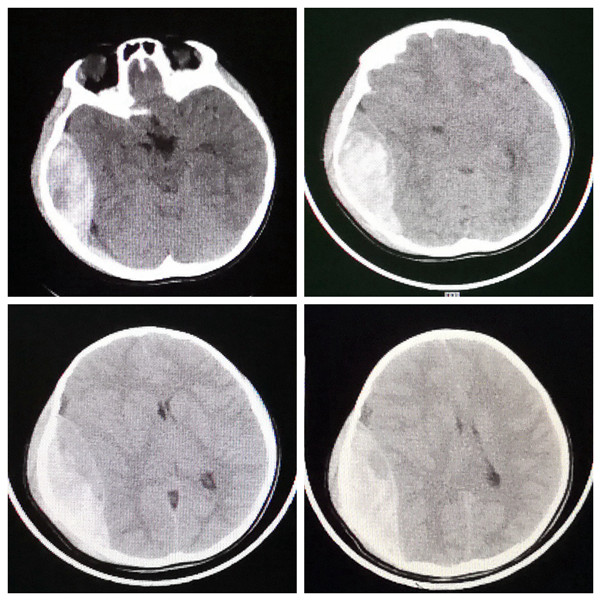

入院时患儿生命体征不稳定,呼吸节律不规则,深昏迷,双侧瞳孔散大,处于濒死状态,命悬一线。接诊的神经外科王举波主治医师立即给予20%甘露醇快速静滴,在巩守平教授、吕健主任医师指导下,迅速为患儿全方位开通绿色通道,联系影像科急诊复查头颅CT,术前影像学评估颅内出血量约110ml,同时联系麻醉手术科,并在急诊科紧急完成必需的术前准备,在麻醉手术科医护人员协助下,王举波主治医师主刀、权瑜主治医师协助,术中清除头皮下血肿80ml、颅内血肿110ml。从术前准备到入室、全麻、开颅、清除血肿、关颅,整个救治过程各个环节无缝衔接。从患儿入院至手术全部结束,共计用时不足3小时,这就是西安交通大学第二附属医院抢救危重病人的速度和效率。令人欣喜的是,患儿术后清醒,住院10天后完全康复出院,未遗留任何功能障碍,家属直呼“奇迹”!